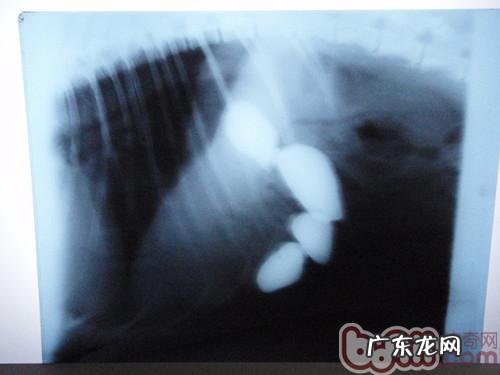

这个是手术前的X光查验 , 清楚的见到四块大小不一的石块躺在它的肚子里 。

X光查验